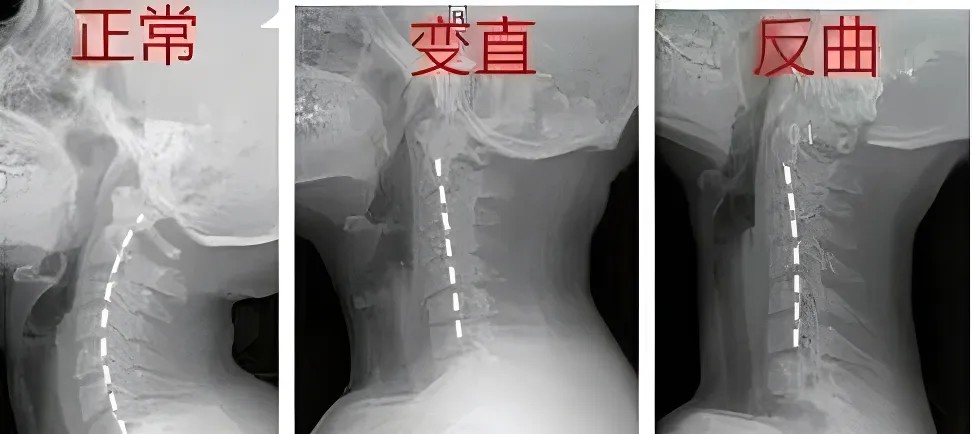

這些報告單上,常寫著“頸椎曲度(弧度)消失”、“頸椎變直”或者是“頸椎曲度反弓”,很多人看到后,一下子就慌了:這頸椎出問題可不是小事,曲度是什么呢?

嬰兒在學習爬行和抬頭的過程中,頸椎的生理曲度逐漸形成,在頸部呈現(xiàn)出一個開口向身體背側(cè)的“C”形;

脊柱的生理曲度就像彈簧一樣,它的存在能有效減輕外力的沖擊震蕩,保護脊髓和大腦,維持姿勢的穩(wěn)定。

頸椎曲度變化給我們帶來的最直接的感受便是反復出現(xiàn)的頸項部板滯發(fā)緊、僵硬酸痛,甚至頭目昏脹,伴或不伴有頸椎“咔咔”響聲。

需要指出的是,單純的“頸椎生理曲度變直”并不是頸椎病,但說明頸椎正處于不健康的狀態(tài),若再不注意,頸椎生理曲度消失,頸椎間盤張力增高,就會導致頸椎纖維環(huán)破裂、椎間盤膨出,誘發(fā)頸椎病。

此外,頸椎曲度變直或者反曲時,頸部肌肉、筋膜等軟組織會發(fā)生改變,也會成為引發(fā)頸椎病的結(jié)構(gòu)與生理基礎。